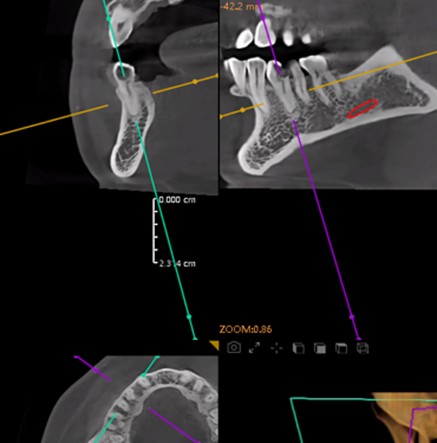

Postoperative CT scans and intraoral photographs were obtained.

November 23, 2025: Implant follow-up examination. The implant surgical site showed excellent healing, with no abnormal bone density around the implant and satisfactory osteogenesis. The third-stage impression taking was implemented. The panoramic radiograph below confirmed the complete seating of the implant impression coping.